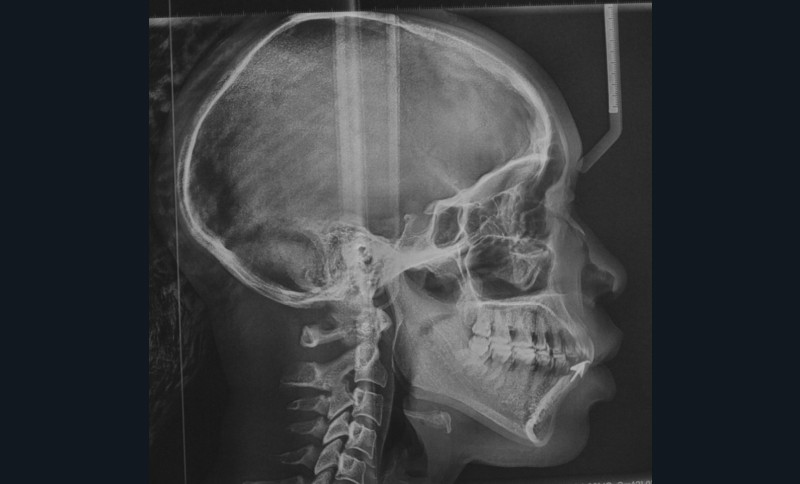

À l’examen clinique et radiologique, elle présente une parodontite de stade 4 grade C avec des poches profondes au niveau des dents 11 et 24, associées à des alvéolyses angulaires atteignant la moitié ou les deux tiers de la hauteur radiculaire au niveau du secteur incisivo-canin maxillaire, et le quart de la longueur radiculaire des premières molaires maxillaires et mandibulaires (fig. 2).

L’analyse céphalométrique de profil révèle des rapports de classe II de Ballard par prognathie maxillaire sur un schéma facial normodivergent associés à une forte proalvéolie mandibulaire (IMPA : 108°) et une légère retroalvéolie maxillaire (I/FH : 108°) (fig. 9 et 10).